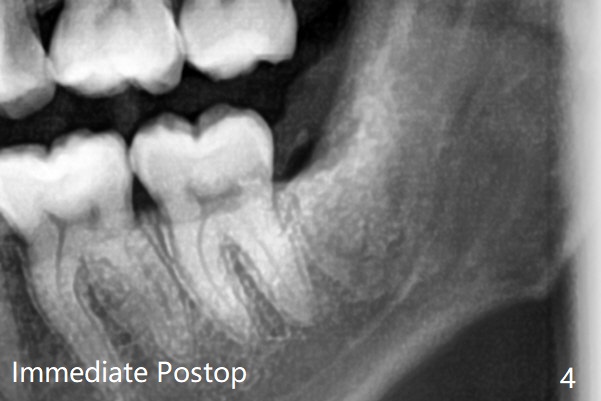

每个牙槽窝放置0.5cc骨水泥(Bone Cement (Bond Apatite from Augma)),覆盖半块胶原塞,4-0铬羊肠线缝合(图四)。